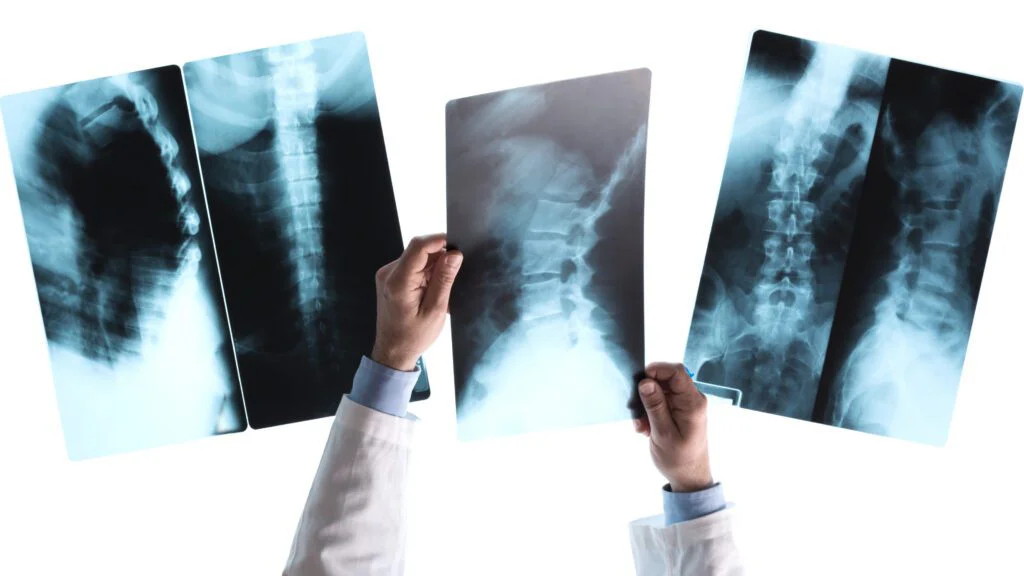

Vynálezy doprovázejí lidstvo po celou dobu jeho existence, neboť umožňují pokrok. Koncem 19. století nastaly obzvlášť přínosné časy, jelikož byla věnována velká pozornost fyzice. Otevřela se tak cesta k mnohem složitějším a převratnějším výzkumům. Jedním z nich byl Röntgenův objev rentgenových paprsků, čímž se výrazně posunula medicína.

Princip, který vedl k zavedení rentgenu, Wilhelm Röntgen objevil náhodou.